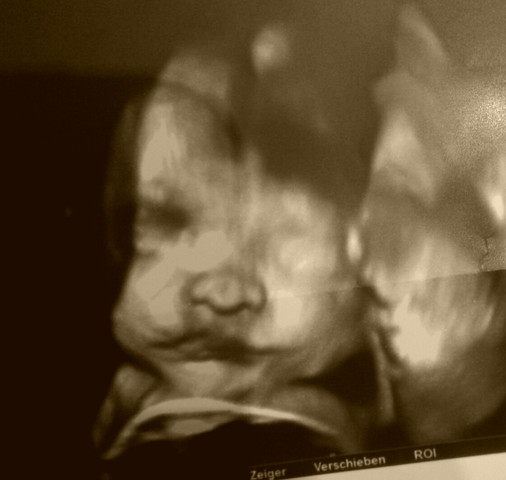

Frühe Zwillingsschwangerschaften im Ultraschall Eineiige Zwillinge in der 55 Schwangerschaftswoche Schwangerschaften entstehen – und das ist nun wirklich nicht überraschend neu – nachdem eine Eizelle von einem Samenfaden befruchtet wurde Zwillinge können auf zwei Arten entstehen. Erfahre, was Dich in der ersten größeren Ultraschalluntersuchung erwartet. 9 SSW Ultraschall Das ist zu sehen Das Baby ist in der 9 SSW ungefähr 16 bis 24 Millimeter lang Auf dem Ultraschall können Sie sogar schon sehen, wo beim Fötus später Finger und Zehen entstehen werden Wird jetzt die erste Ultraschalluntersuchung durchgeführt, lässt sich auch feststellen, ob vielleicht sogar Zwillinge unterwegs sind.

Vielleicht erfahren Sie das erst, wenn die Kinder geboren sind Aber man kann per Ultraschall schon einiges feststellen SSW 5 evtl. 9 SSW – Entwicklung des Körpers & Ultraschall Der dritte Schwangerschaftsmonat wird mit der 9SSW eingeläutet Zum Ende dieser Woche werden die wichtigsten Organe des Babys vollständig entwickelt und der bis zur 8SSW sichtbare Schwanz zurückgebildet sein Die bis zur Geburt andauernde Fötalphase beginnt jetzt und das Ungeborene wird von nun an nicht mehr Embryo, sondern Fötus genannt. Frühe Zwillingsschwangerschaften im Ultraschall Eineiige Zwillinge in der 55 Schwangerschaftswoche Schwangerschaften entstehen und das ist nun wirklich nicht überraschend neu nachdem eine Eizelle von einem Samenfaden befruchtet wurde ;.